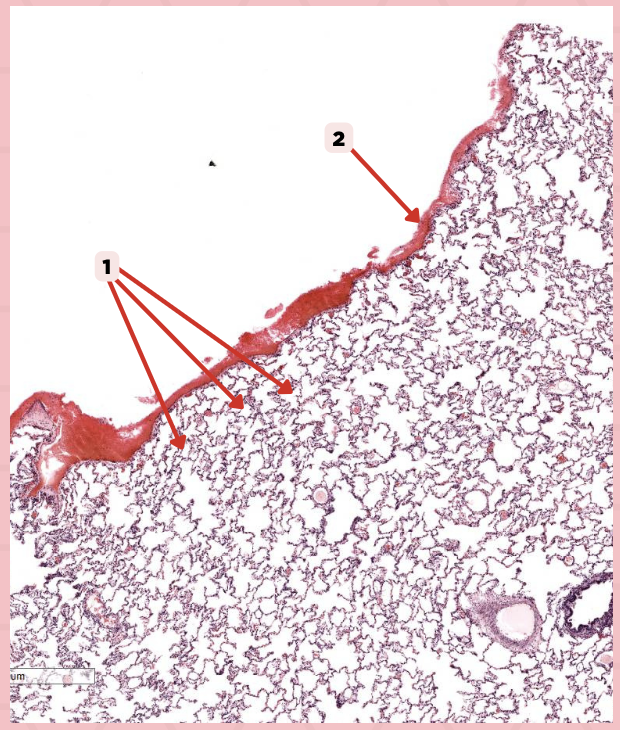

Simple squamous epithelium (Mesothelium)

The surface related to the pleural cavity is in line with what type of epithelium?

Lumens and Interalveolar septa

Name the irregular spaces and the fine threads of tissue that separate them.

Visceral pleura

Identify the structure labeled as 1.

Alveoli

Visceral Pleura

What type of pleura is a thin layer of connective tissues that borders on the outside by mesothelium?

Simple Squamous Epithelium

What epithelium lines the red arrow?

Mesothelium

Identify the structure labeled as 1.

Pulmonary Capillaries

Oxygenated blood is collected by structure #2 from what source/structure?